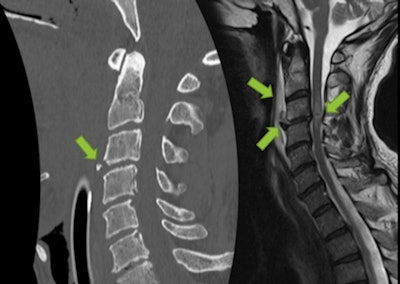

Traumatic injury in 53-year-old man after ski fall (GCS 6/15 onsite). Normal initial brain CT scan, but clinical evaluation was impossible due to intubation onsite. CT revealed teardrop fracture on C3 and subtle retrolisthesis of C3 over C4, suggesting hyperextension discoligamentous injury. MRI confirmed rupture of anterior longitudinal ligament, discal extrusion into prevertebral space, and a hemorrhagic spinal contusion at C3-C4 level. Patient was found to be tetraplegic after extubation."The mechanism of injury determines the distribution of injury levels and thus influences the degree of neurologic deficit," they commented.